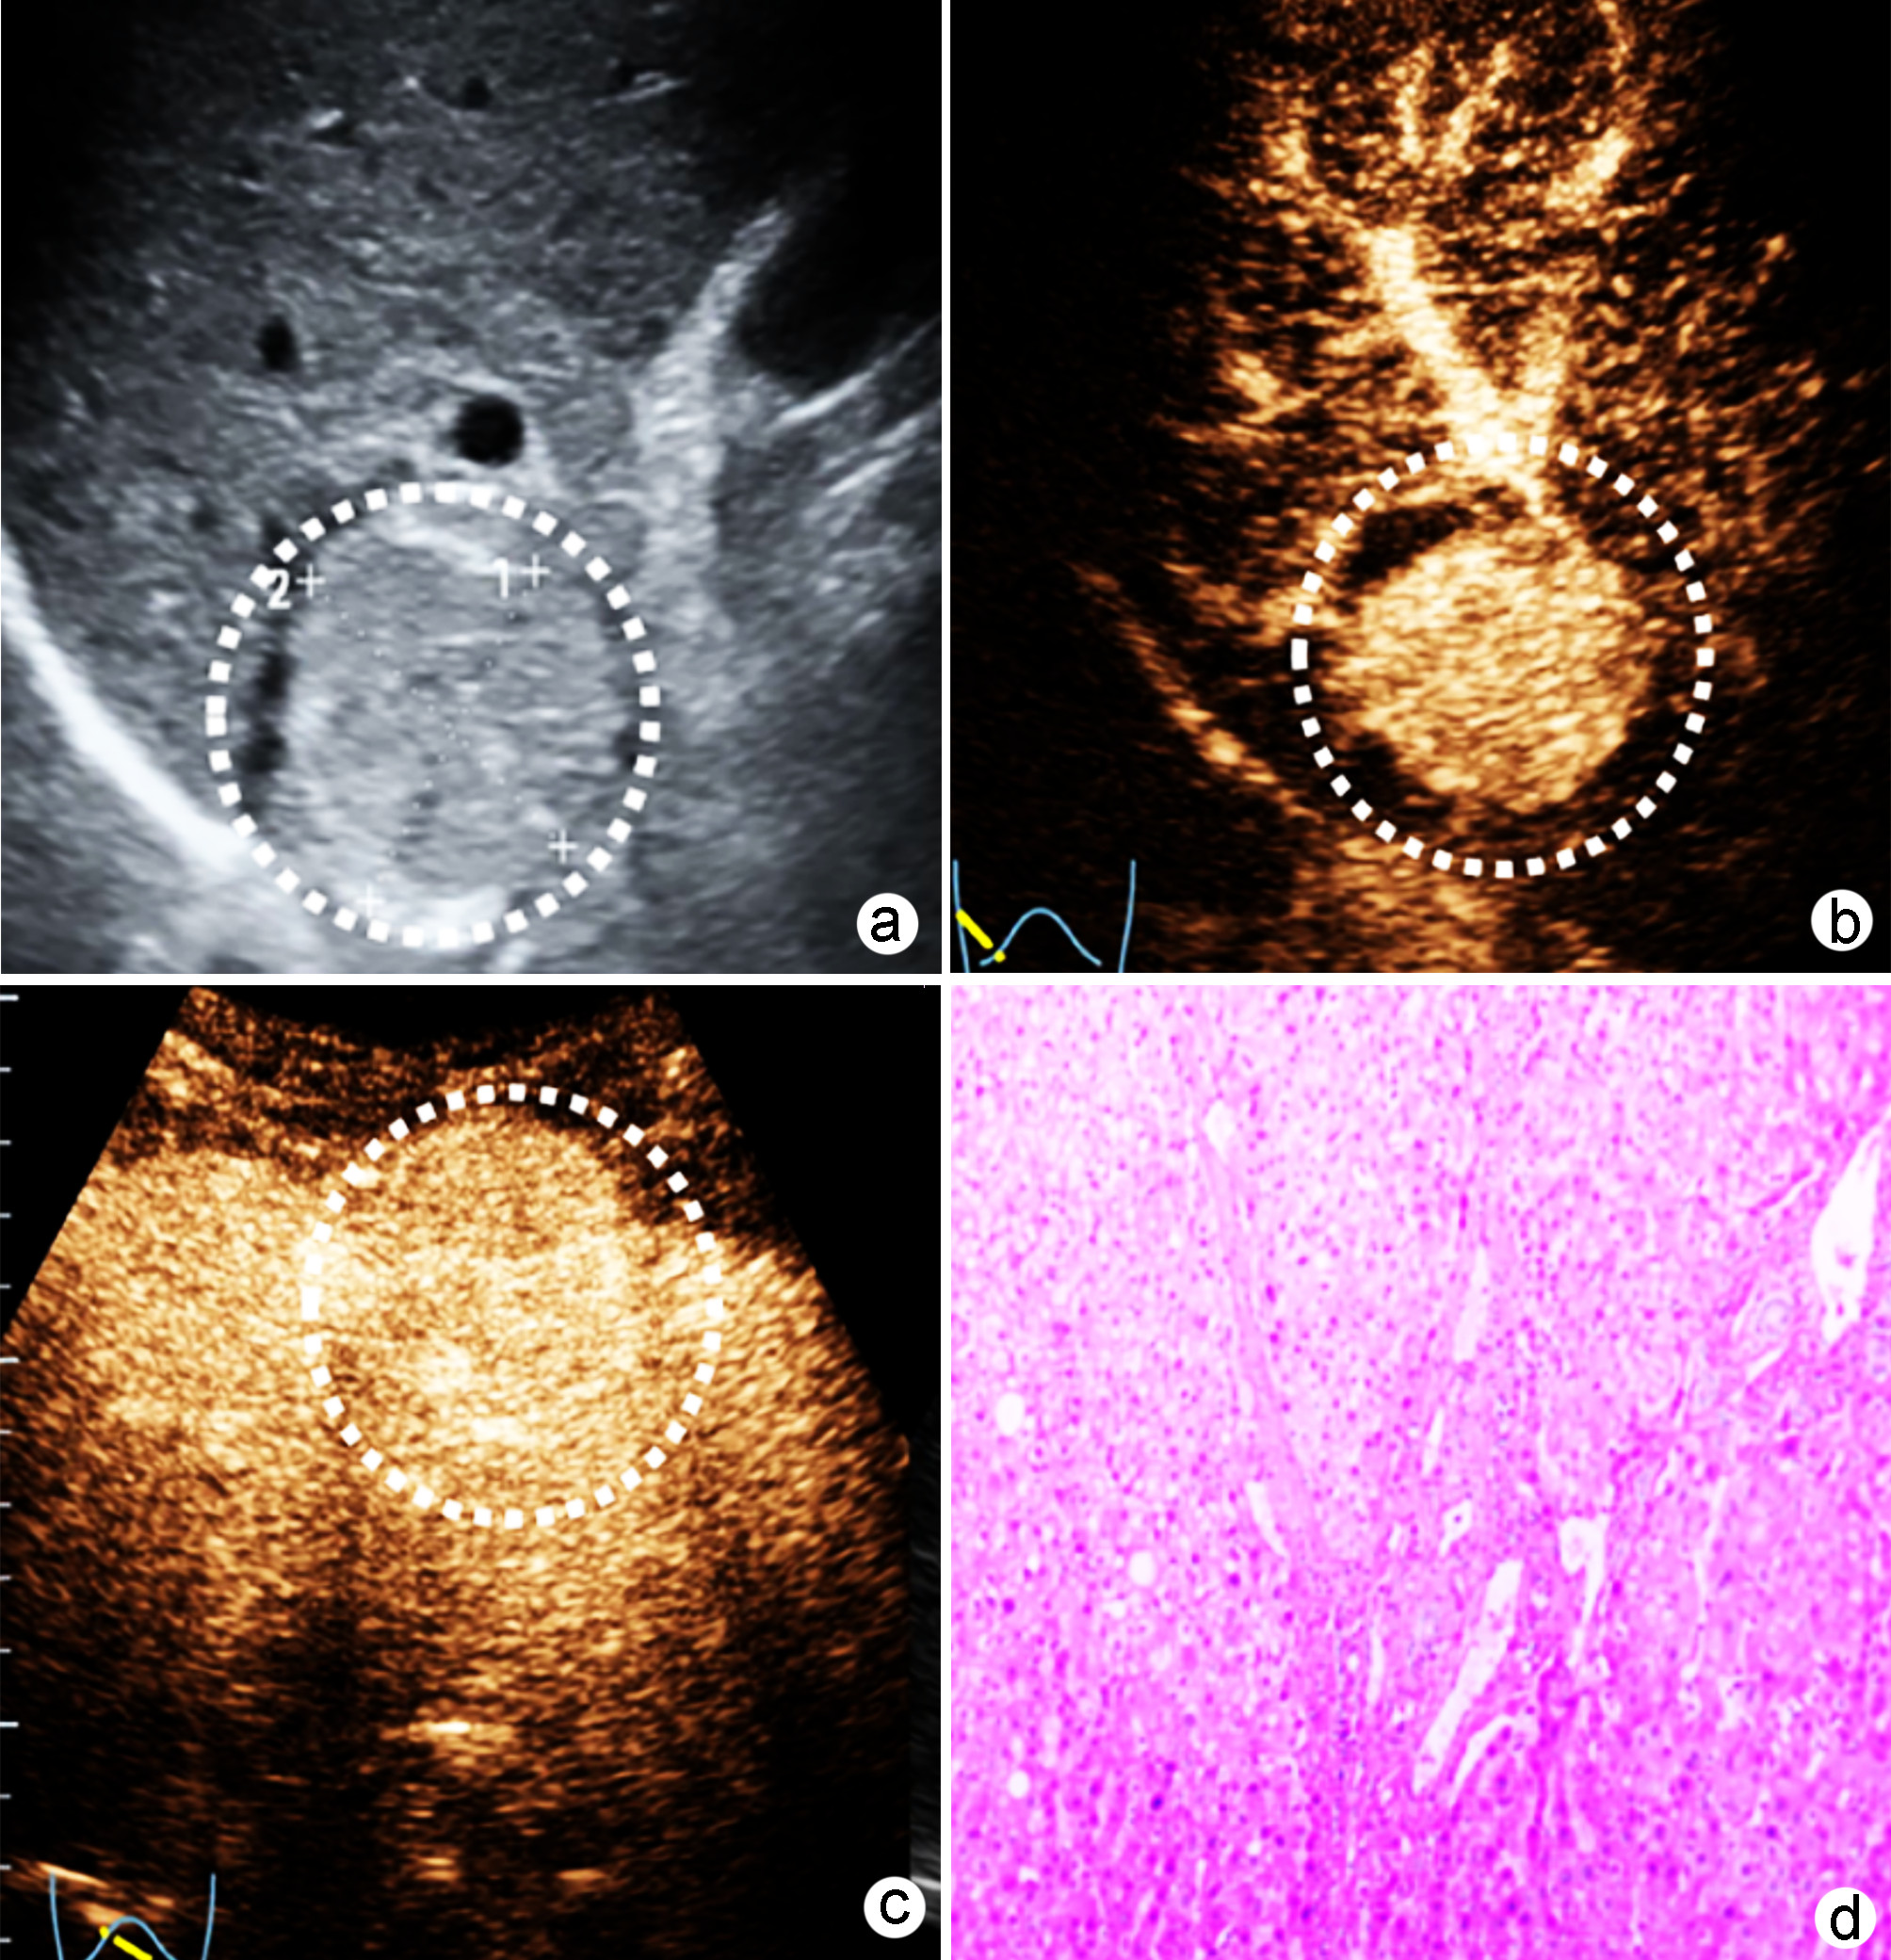

Construction and validation of a nomogram model for microvascular invasion in hepatocellular carcinoma based on the characteristics on contrast-enhanced ultrasound Liver Imaging Reporting and Data System

Jing XI, Meiqin GU, Zuowei BAO

2022, 38(11): 2520-2525. DOI: 10.3969/j.issn.1001-5256.2022.11.016

Abstract(882) HTML (344) PDF (2938KB)(62)

Abstract:

Objective  To construct and validate a nomogram model for predicting microvascular invasion (MVI) based on the characteristics on contrast-enhanced ultrasound (CEUS) Liver Imaging Reporting and Data System (LI-RADS) in patients with hepatocellular carcinoma (HCC).  Methods  A total of 262 patients with HCC who were diagnosed in Wujin Hospital Affiliated to Jiangsu University from January 2017 to July 2020 were enrolled and randomly divided into modeling group and validation group at a ratio of 1∶ 1, with 131 patients in each group. MVI was confirmed by postoperative microscopic pathological results, and there were 70 patients with MVI in the modeling group and 56 patients with MVI in the validation group. CEUS was used to evaluate LI-RADS characteristics for the two groups. The independent samples t-test was used for comparison of continuous data between the two groups, and the chi-square test was used for comparison of categorical data between the two groups. Univariate and multivariate Logistic regression analyses were used to identify the risk factors for MVI in the modeling group; the receiver operating characteristic (ROC) curve was plotted, and the area under the ROC curve (AUC) was calculated for the model in predicting MVI to evaluate the accuracy of prediction; a decision curve analysis was used to evaluate the consistency of the model, and dispersion was compared between the calibration curve and the standard curve for the model in predicting MVI.  Results  There were no significant differences in clinical data and CEUS findings between the modeling group and the validation group (all P > 0.05). The univariate analysis showed that compared with the MVI-negative patients, the MVI-positive patients had significant increases in serum alpha fetoprotein (AFP) level, tumor diameter, and LR-5 "late and mild washout" and LR-M "early washout" on LI-RADS, as well as a significantly higher LI-RADS grade (all P < 0.05). The multivariate analysis showed that AFP 20-400 ng/mL (odds ratio [OR]=2.65, P < 0.001), AFP≥400 ng/mL (OR=3.98, P < 0.001), tumor diameter ≥30 mm (OR=2.12, P < 0.001), and LR-M on CEUS (OR=3.24, P < 0.001) were independent risk factors for MVI. The ROC curve analysis showed that the nomogram had an AUC of 0.867 and 0.821 in predicting MVI in the modeling group and the validation group, respectively. The nomogram model had a C-Index of 0.765 (95% confidence interval: 0.701-0.834). The calibration curves of the nomogram model were close to the standard curve in both groups.  Conclusion  The nomogram model based on LI-RADS obtained by CEUS in combination with AFP and tumor diameter has a good application value and can guide the preoperative screening for patients at a high risk of MVI and the development of appropriate surgical plans in clinical practice.